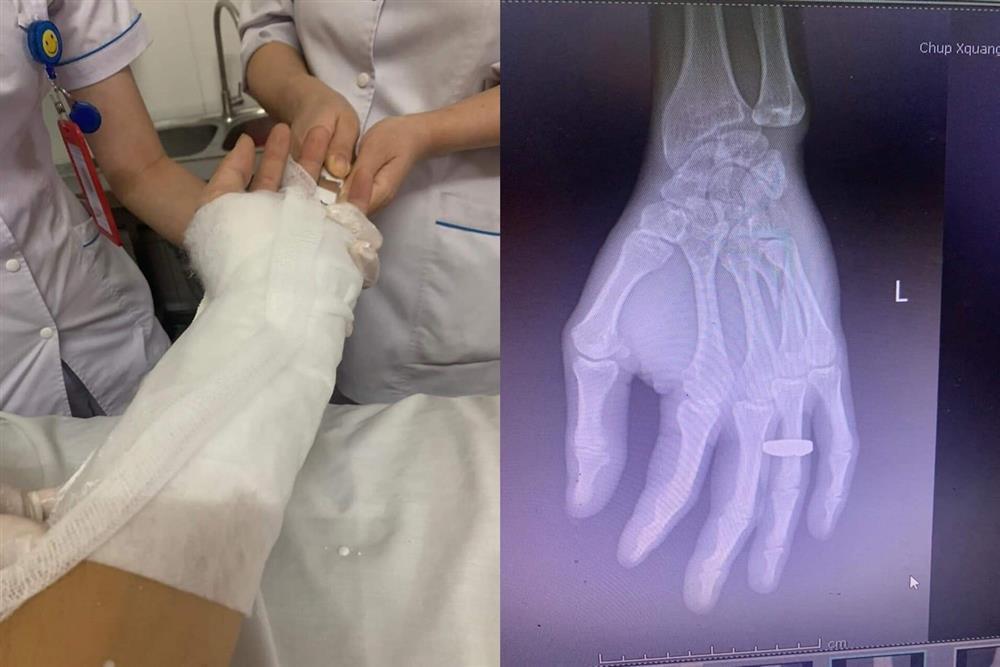

Hậu quả, nam hành khách bị gãy tay, đa chấn thương. Anh ta còn đuổi người này xuống khi xe mới chỉ chạy đến Bắc Ninh.

Hình ảnh gãy tay của khách nam